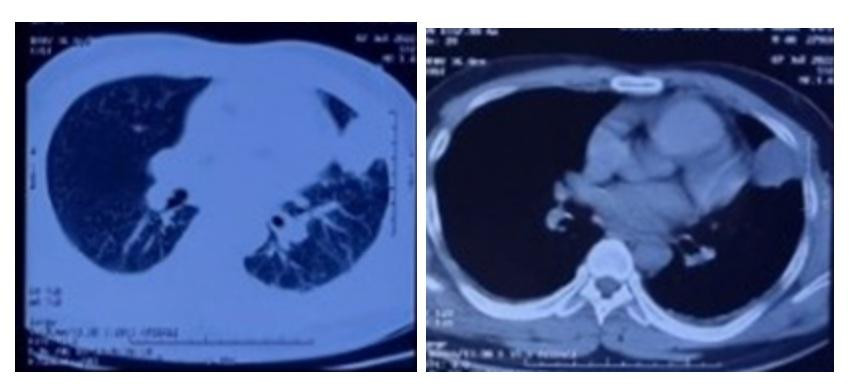

| Hình ảnh phim chụp cắt lớp vi tính lồng ngực của bệnh nhân. |

Sau đó, bệnh nhân được làm các xét nghiệm: công thức máu, cấy đờm, cấy máu, chụp X quang tim phổi và chụp cắt lớp vi tính lồng ngực. Kết quả: Bạch cầu máu tăng cao, biểu hiện tình trạng nhiễm trùng nặng: 35 G/L, N 82,4%, CRP 215, siêu âm kết quả theo dõi ổ áp xe sát thành ngực trái kích thước 5 x 6 cm.